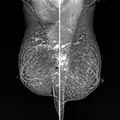

| Silicone granuloma | |

| Snowball like hyperechogenic axillary lymph nodes in a woman with silicone implants removed due to complications | |